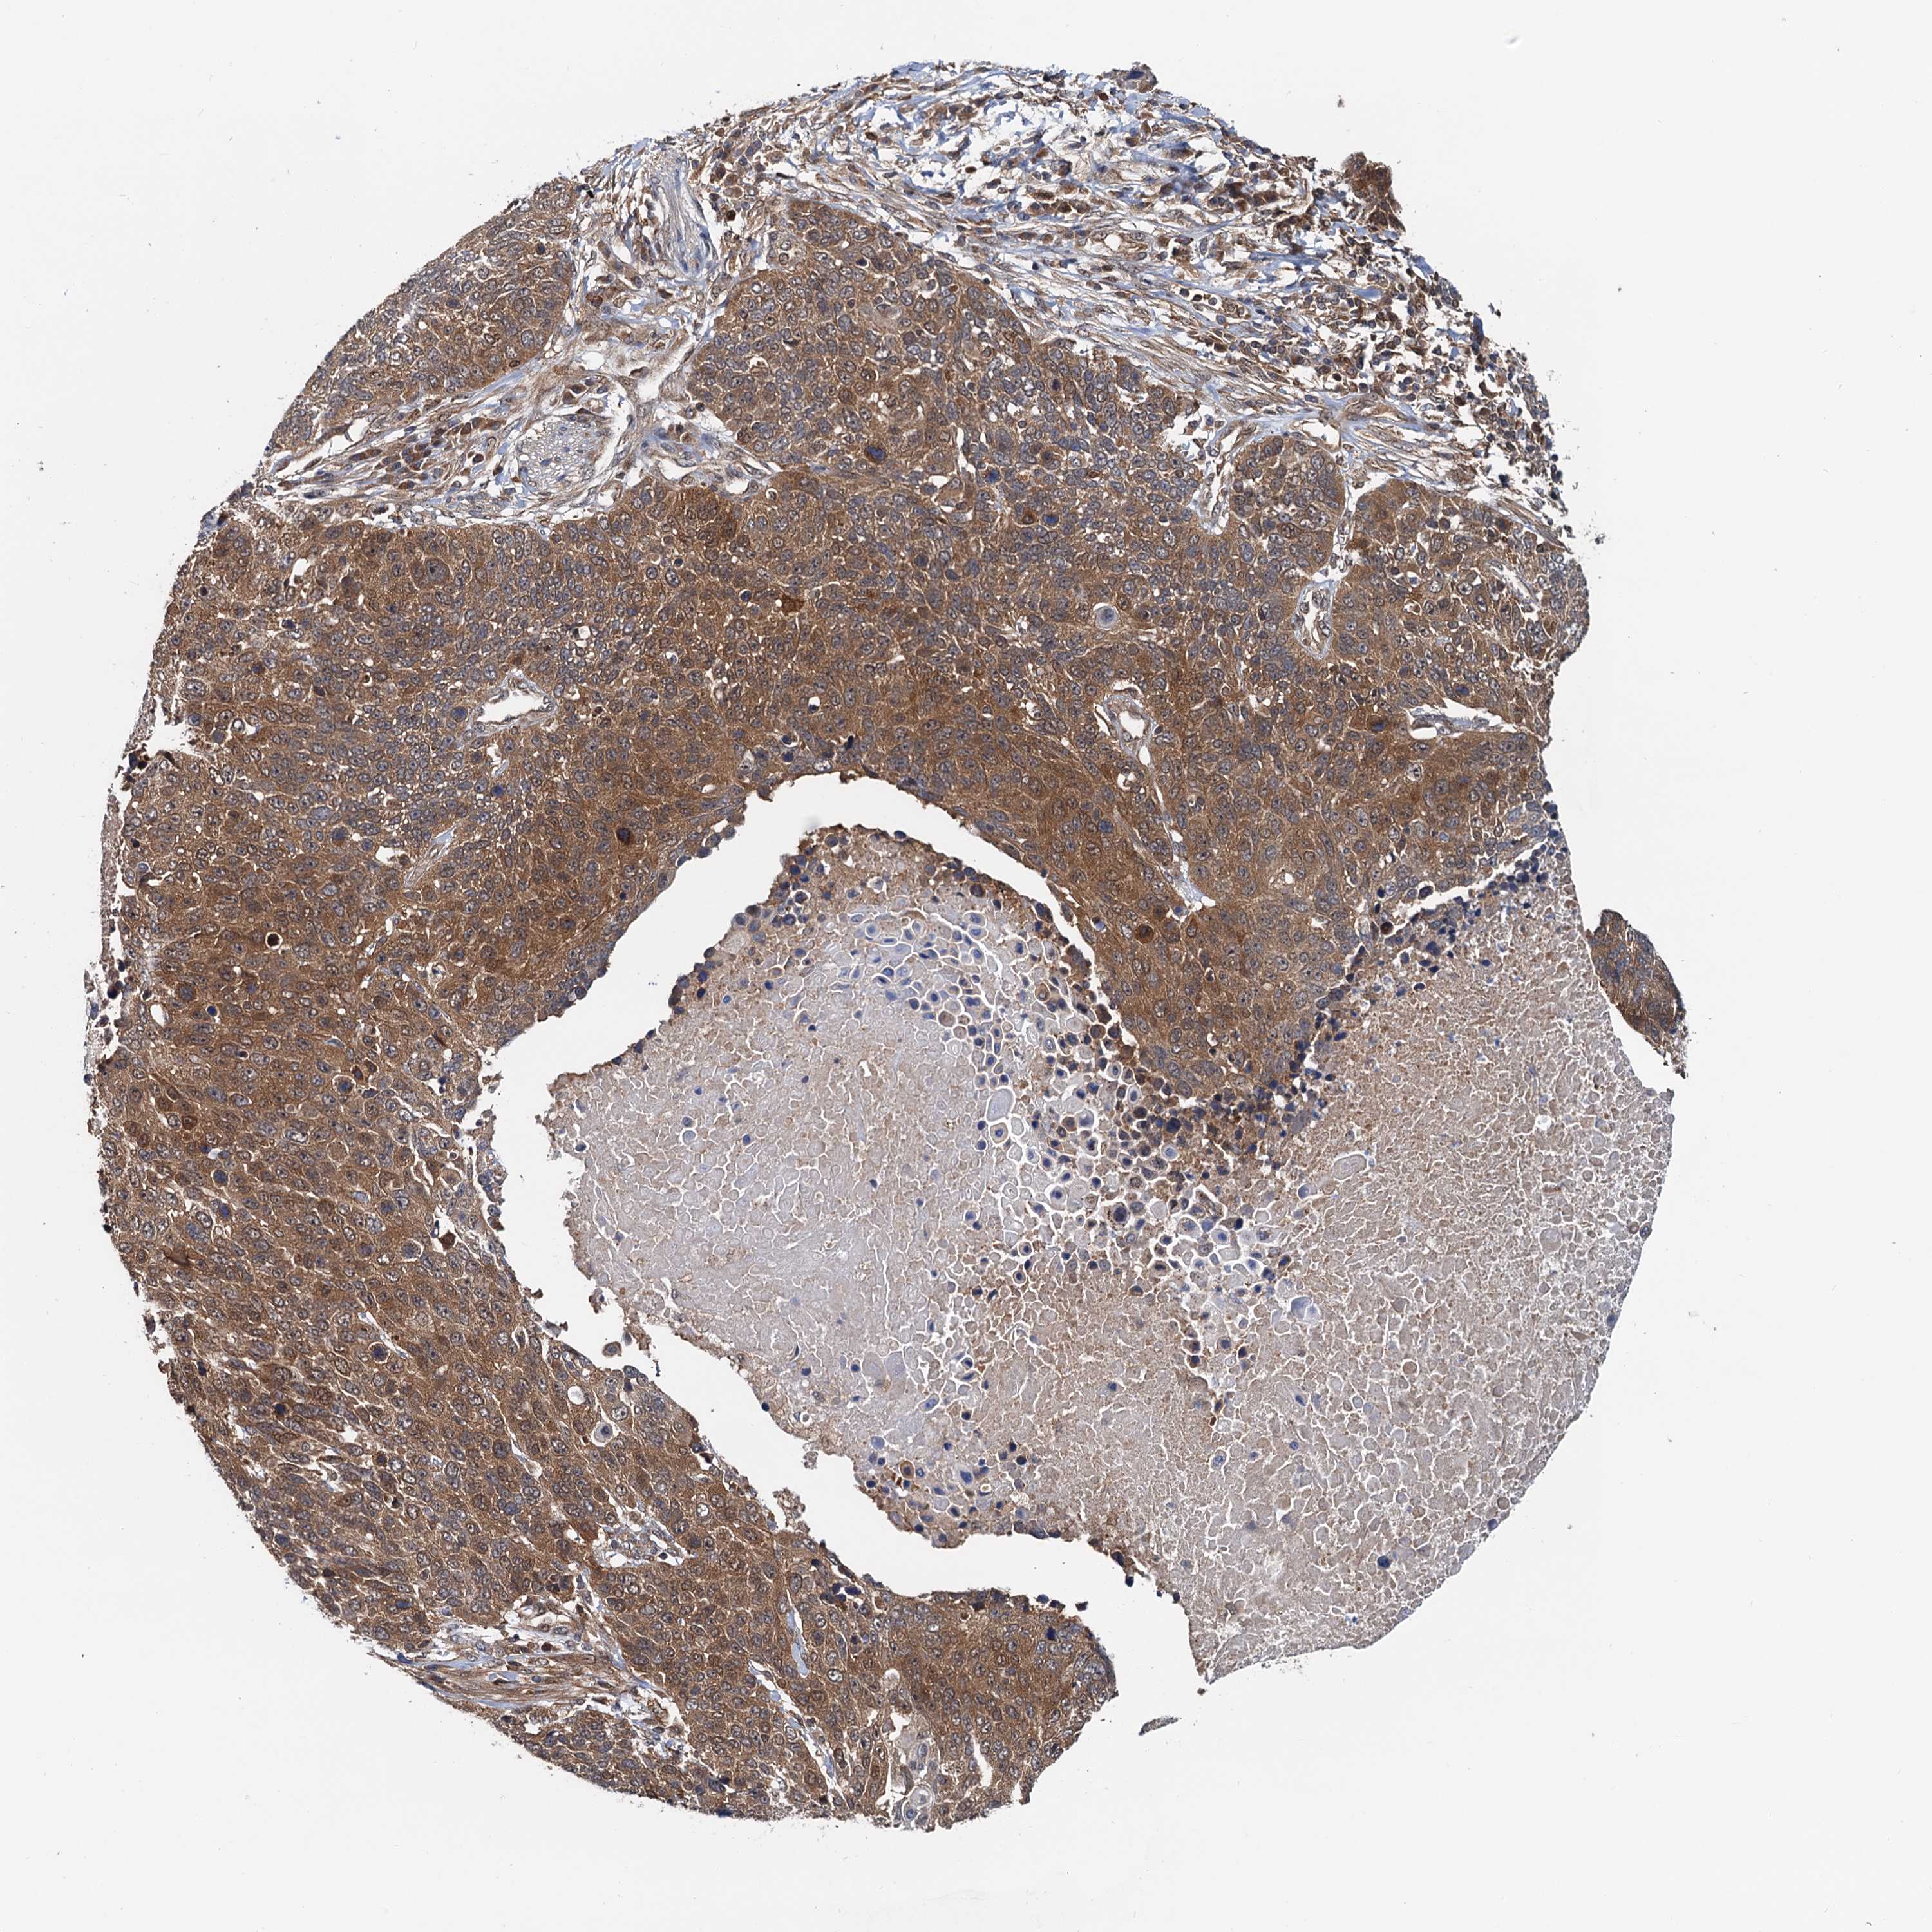

LUNG SQUAMOUS CELL CARCINOMA (TCGA) - Interactive survival scatter ploti

The Survival Scatter plot shows the clinical status (i.e. dead or alive) for all individuals in the patient cohort, based on the same data that underlies the corresponding Kaplan-Meier plots. Patients that are alive at last time for follow-up are shown in blue and patients who have died during the study are shown in red.

The x-axis shows the expression levels (FPKM) of the investigated gene in the tumor tissue at the time of diagnosis. The y-axis shows the follow-up time after diagnosis (years). Both axes are complimented with kernel density curves demonstrating the data density over the axes. The top density plot shows the expression levels (FPKM) distribution among dead (red) and alive patients (blue). The right density plot shows the data density of the survived years of dead patients with high and low expression levels respectively, stratified using the cutoff indicated by the vertical dashed line through the Survival Scatter plot. This cutoff is automatically defined based on the FPKM cutoff that minimizes the p-score. The cutoff can be changed by dragging the vertical line or by entering a cutoff value in the square labeled "Current cut-off".

Under the Survival Scatter plot the p-score landscape (black curve; left axis) is shown together with dead median separation (red curve; right axis). Dead median separation is the difference in median mRNA expression between patients who have died with high and low expression, respectively. It is calculated as follows: median FPKM expression of dead patients with high expression - median FPKM expression of dead patients with low expression. This is intended to aid the user in visually exploring custom cutoffs and the associated p-scores and dead median separation.

Individual patient data is displayed and can be filtered by clicking on one or more of the category buttons on the top of the page. Categories describing expression level and patient information include: high, low, alive, dead, female, male and tumor stages. The scale of the x-axis can be toggled between linear and log-scale by clicking on the "x log" button. Mouse-over function shows TCGA ID, patient information and mRNA expression (FPKM) for each patient.

& Survival analysisi

Kaplan-Meier plots summarize results from analysis of correlation between mRNA expression level and patient survival. Patients were divided based on level of expression into one of the two groups "low" (under cut off) or "high" (over cut off). X-axis shows time for survival (years) and y-axis shows the probability of survival, where 1.0 corresponds to 100 percent.

AAGAB is not prognostic in Lung Squamous Cell Carcinoma (TCGA)

: 31.01

P scorei

N/A

Average pTPM 36.7

Number of samples 489